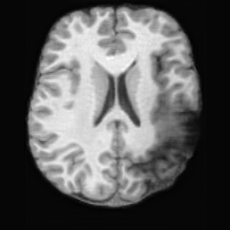

(a)PathologicalInput ImageSynthSR [18]Brain-ID [28]UNA [30]USBHealthyGround TruthRefer to captionRefer to captionRefer to captionRefer to captionRefer to captionRefer to captionRefer to captionRefer to captionRefer to captionRefer to captionRefer to captionRefer to captionRefer to captionRefer to captionRefer to captionRefer to captionRefer to captionRefer to captionRefer to captionRefer to captionRefer to captionRefer to captionRefer to captionRefer to caption(b)HealthyInput ImageConditionalLesion MaskUNA [30]USBRefer to captionRefer to captionRefer to captionRefer to captionRefer to captionRefer to captionRefer to captionRefer to captionRefer to captionRefer to captionRefer to captionRefer to captionRefer to captionRefer to captionRefer to captionRefer to caption

Figure 5: Comparison of bidirectional brain editing. (a) pathology-to-healthy, the circles and arrows highlight lesion regions and unsuccessful reconstructions; (b) healthy-to-pathology. Note that SynthSR and Brain-ID cannot perform healthy-to-pathology editing.

Healthy-to-Pathology Editing. As shown in Fig. 5 (b), given a healthy brain image paired with a random lesion mask, USB seamlessly embeds the lesion into the healthy anatomy, producing realistic pathological appearances consistent with surrounding structural context. Yet UNA’s syntheses are visually unrealistic, with the conditioned lesion mask simply overlaid as a parallel layer onto the healthy brain. Tab. 3 further demonstrates USB’s superior performance. The evaluation was conducted on 100 pairs of lesion masks and healthy brains, with real stroke images